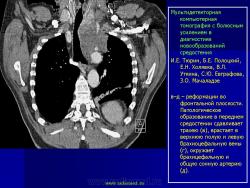

Продолжение.